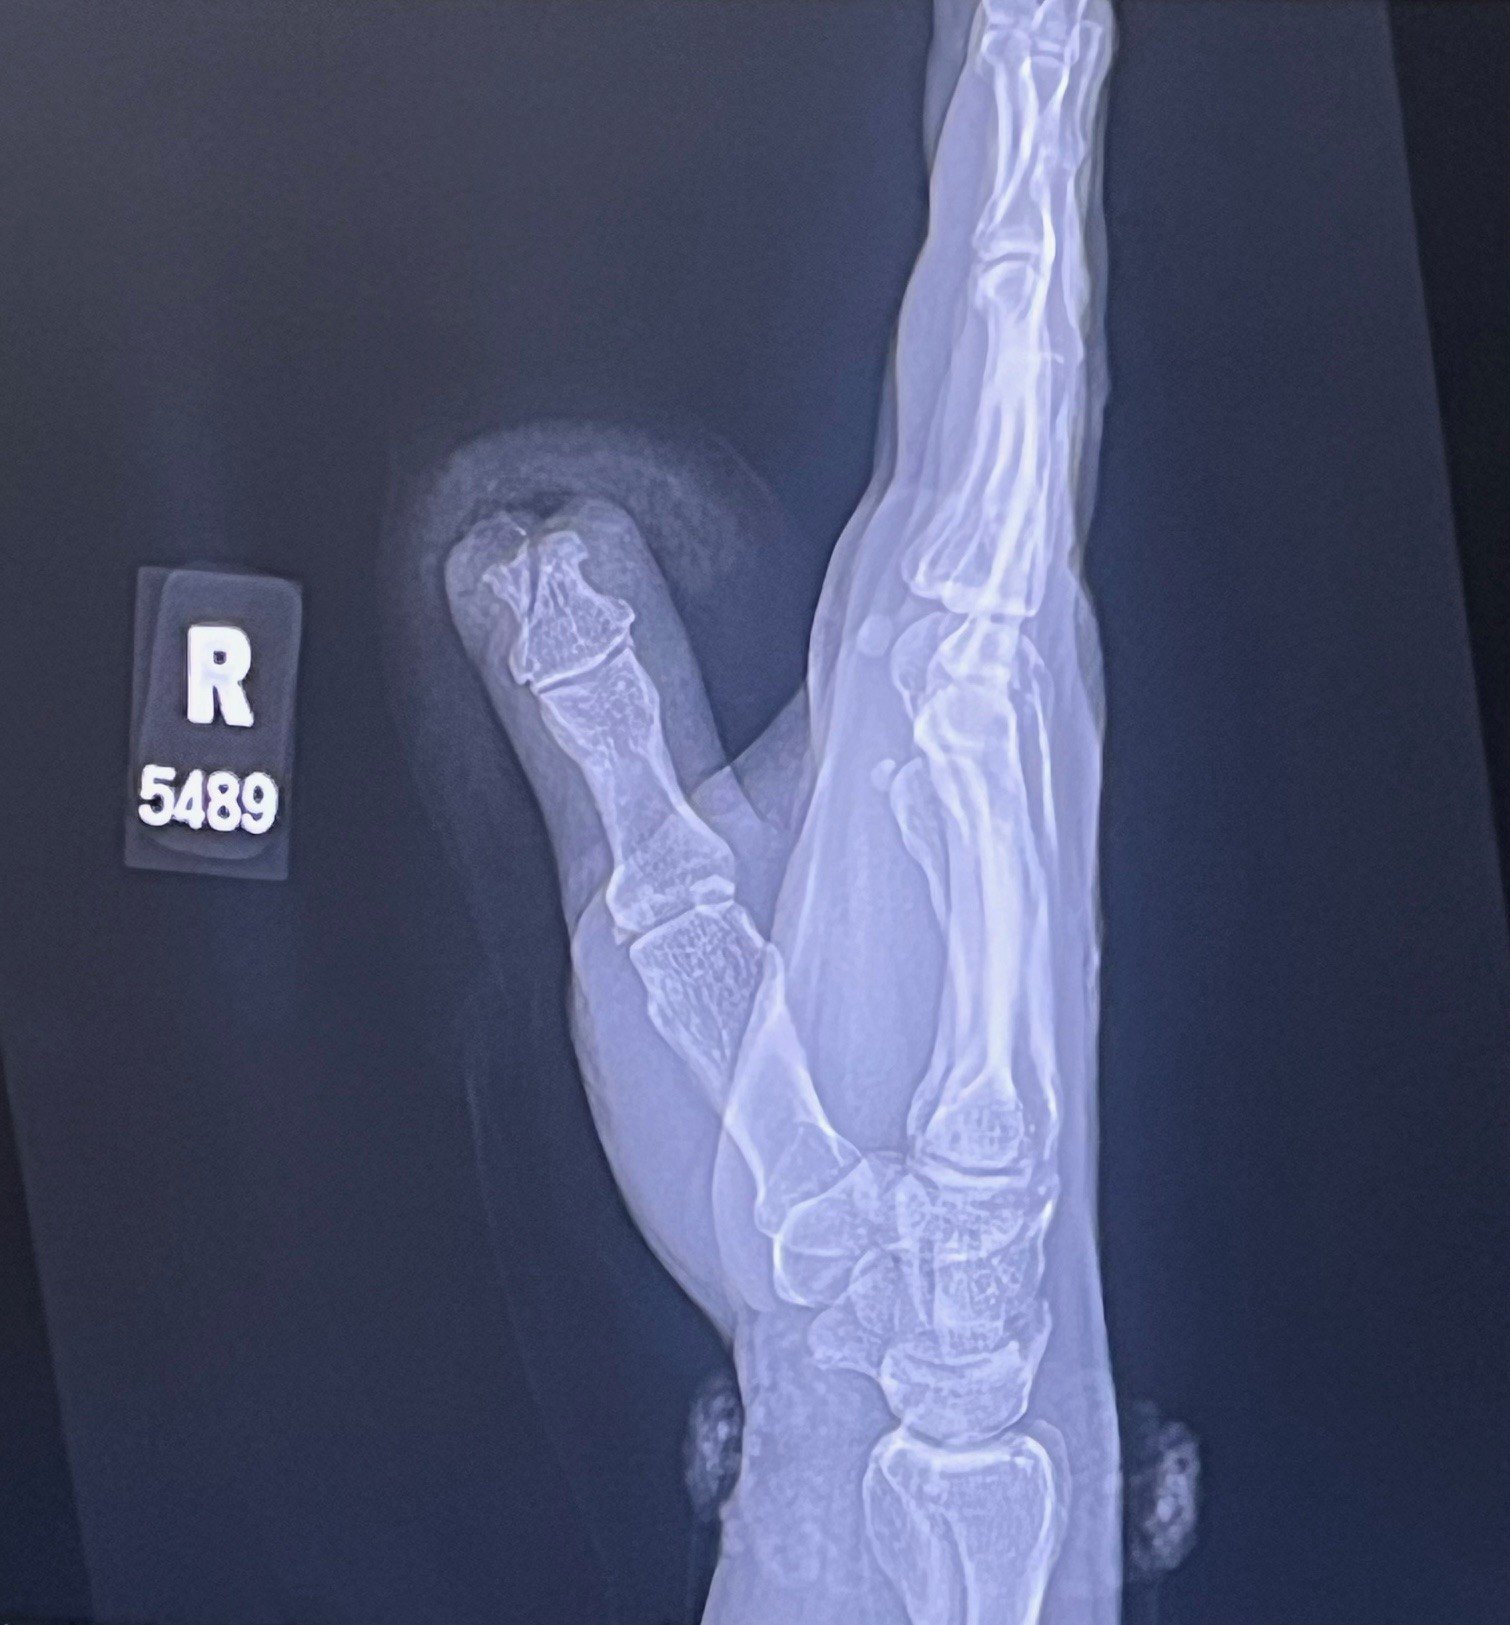

I am grateful that I didn't lose more of my thumb. I am grateful that I kept the dogs off of my daughter. I am grateful that I got hurt and not my wife or the kids. I am most certainly not happy, but I am grateful. Anyway... I could certainly use some thoughts and mojo in the coming weeks.

Basically, from where my nail started is now gone. There was no way to save the tip, and the bones below had been shattered. On the 24th, I saw a plastic surgeon in an attempt to save what was left of the finger. I am hopeful that with some time and work, I will be back to my usual level of sucking at guitar...lol! If not, I guess I'll have to slow down, turn the gain down and invest in some tan pants...